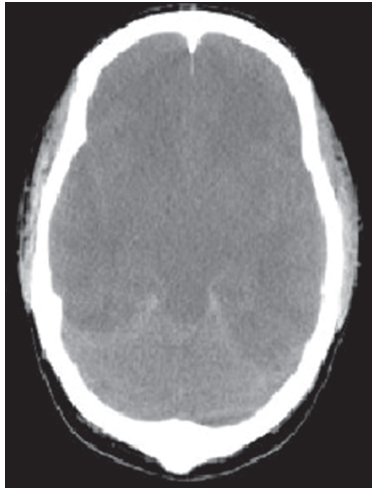

A 3-month-old infant was brought for evaluation after the sudden development of a tonic-clonic seizure that involved the left upper extremity.